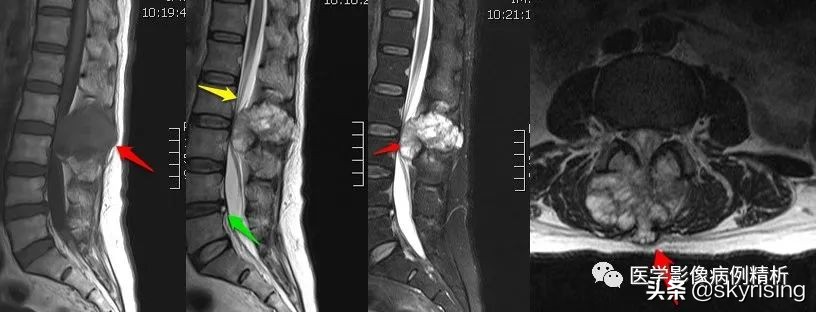

MRI增强

T1WI矢状位红色箭头所示腰2-3椎体附件区团块状异常信号,T1低信号为主,信号不均,T2WI高信号为主,其内见条形低信号分隔,压脂像明显高信号为主,向前突入椎管,临近蛛网膜下腔扩张呈三角形,相应水平椎管变窄,脊髓受压前移,信号增高,向后直达皮下脂肪层。轴位像椎体棘突、双侧椎弓根骨质破坏,见团块状软组织信号,病灶突入椎管内,相应水平椎管变窄,信号明显不均,其内见多发条形低信号,双侧竖脊肌受压移位。

黄色箭头所示蛛网膜下腔明显扩张, 病灶上下缘呈三角形扩张,脊髓受压信号增高,提示损伤。

绿色箭头可见腰4-5椎间盘髓核 T2 信号减低(注意其他椎间盘),提示间盘变性,纤维环后缘见点状T2及压脂像高信号,T1低信号,提示纤维环撕裂,需警惕椎间盘脱出可能。

红色箭头汇总:腰2-3椎体附件包括棘突、双侧椎弓根骨质破坏,见团块状软组织肿物,T1低信号,T2及压脂像高信号,信号不均,中心见多发条形低信号分隔。病灶向前突入椎管内,蛛网膜下腔扩张,脊髓受压前移、信号增高,向后达皮下脂肪层。轴位像病灶推移双侧竖脊肌,呈分叶状生长。

黄色箭头汇总:病灶向前突入椎管,推移脊髓,蛛网膜下腔扩张。

绿色箭头汇总:腰4椎体纤维环后缘见点状高信号,提示撕裂。